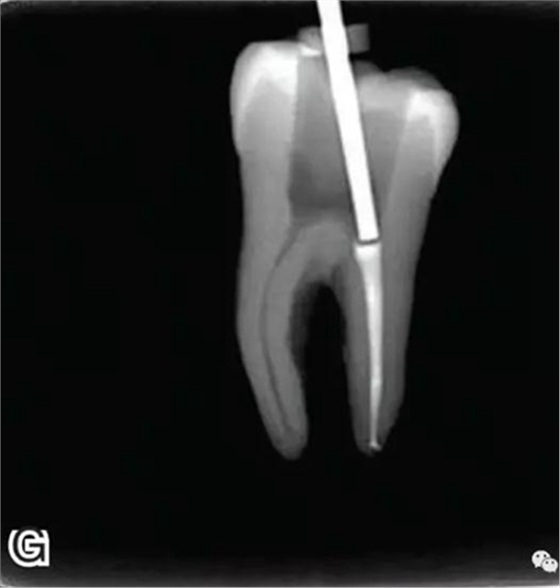

8、熱牙膠根中上段的充填

在完成根尖段的充填后,使用熱塑牙膠注射儀對(duì)根管中上段進(jìn)行分層充填,一般分2~3次完成充填,每次充填均使用相應(yīng)直徑大小的垂直加壓器進(jìn)行加壓。拍片確認(rèn)充填效果(圖8)。

圖8 熱牙膠根中上段的充填,A、B.注射儀注射中段熱牙膠

C、D.垂直加壓器加壓 E、F.注射儀繼續(xù)注射上段熱牙膠

G、H.垂直加壓器加壓 I、J.完成根中上段的充填